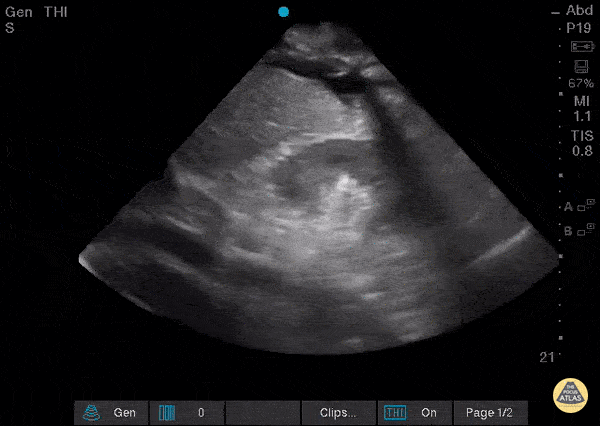

Pulmonary - Diaphragmatic Contraction

A 61-year-old female with history of chronic Hepatitis C, end-stage liver disease, and pulmonary hypertension presented to the emergency department complaining of increasing dyspnea and abdominal distension over the last 10 days. Point-of-care ultrasonography of the right upper quadrant showed large anechoic fluid collections in the pleural space and intra-abdominal cavity, with a "spine" sign visible and with distinct “flopping” of the diaphragm over the caudal tip of the cirrhotic liver with each respiratory cycle. A great view of diaphragmatic contraction in a patient with dyspnea! Scott Brensel, MS-IV, Touro College of Osteopathic Medicine California